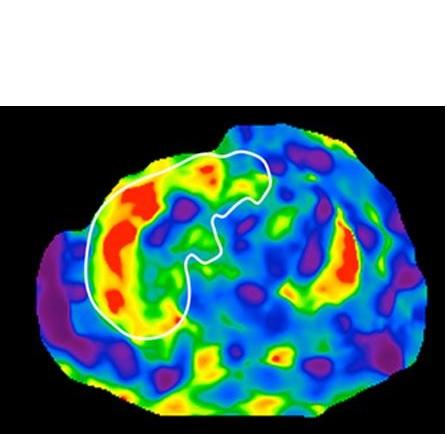

- le test permet même de différencier l’existence d’un parent au premier degré atteint, d’une cirrhose non diagnostiquée avec une précision de 87% ; ces résultats sont ici confirmés par imagerie par résonance magnétique (IRM : voir visuel ci-contre de scanner du foie avec cirrhose).